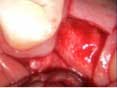

Case 1: Osteotome sinus lift with simultaneous implant placement

A 53-year-old female with a medical history of hypothyroidism, seasonal allergies, and asthma taking Synthroid and Singula presented to my office with pain in No. 3, failed root canal therapy, and a fracture. The tooth was deemed hopeless and extraction and implant placement was treatment planned. Under local anesthesia, tooth No. 3 was sectioned into three pieces and extracted. The sockets were debrided, filled with gel foam, and closed with chromic gut sutures. Healing was uneventful. The patient did not return for two years for follow-up. A CT scan was taken, which confirmed that approximately5 mm of bone remained below the floor of the sinus. After reviewing the options with the patient, a treatment plan of an internal sinus lift (osteotome), bone graft, platelet-rich fibrin (PRF) and simultaneous implant placement was agreed upon. Under local anesthesia, a full thickness flap with two vertical releasing incisions was performed at tooth No. 3 site. A trephine bur was used to a depth of 4 mm. An osteotome was then employed to infracture the bone core, which remained attached to the Schneiderman membrane. A bone graft consisting of DFDBA, anorganic bovine bone, and PRF was used in the osteotomy to increase the vertical bone height using sequential osteotomes. After sufficient elevation, a 7x9 tapered implant was placed on low speed to 50% of the implant depth. The remaining placement of implant was done with a hand torque on 50 ncm to allow for further expansion of the alveolar housing. A healing abutment was placed using the principles of platform switching. Healing was uneventful, and integration was successful.

Case 1: Implant and osteotome bone graft through the socket with Southern Implant